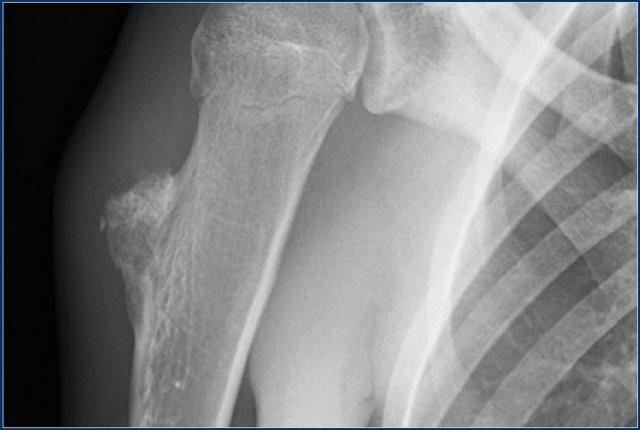

Đây là tổn thương nằm ở vùng đầu xương và hành xương của đầu trên xương cánh tay.

Tổn thương chủ yếu bị vôi hóa.

Hình ảnh T1W mặt phẳng vành tai cho thấy bờ tổn thương có dạng thùy và tín hiệu thấp ở ngoại vi do các vôi hóa.